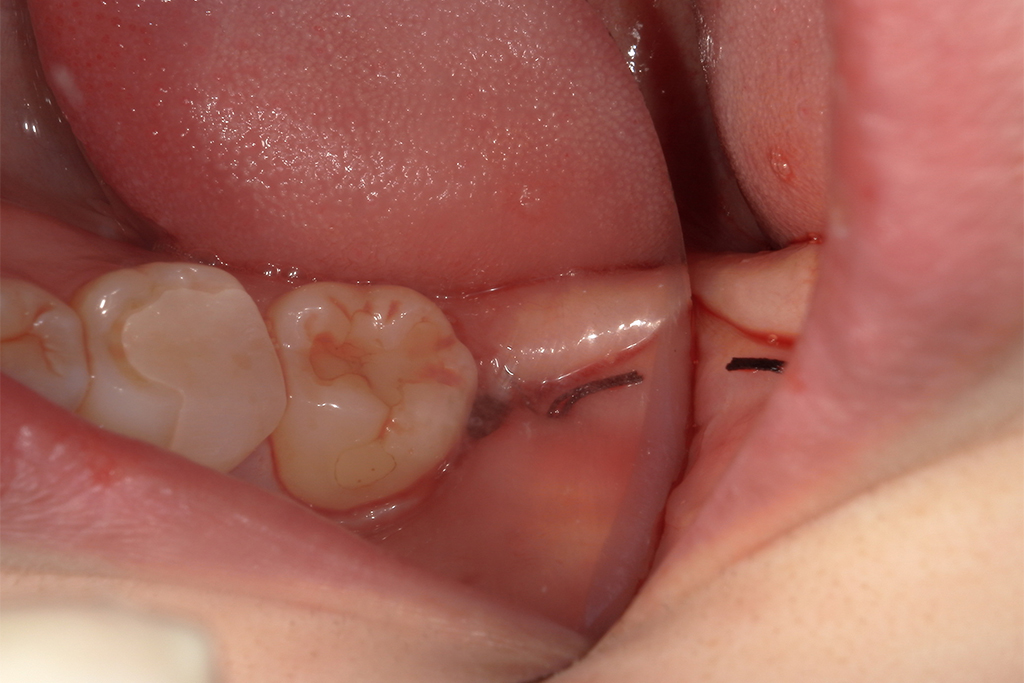

| 患者の年齢 | 30歳 |

|---|---|

| 症状 | 親知らずが痛い。横向きに生えている |

| 治療内容 | 親知らず抜歯1本 |

| 費用 | 約8,500円 (検査料、CT費、処置料、処方箋費用) |

| 治療期間 | 1日 |

| デメリット・ リスク |

麻痺が起こる場合がある、痛みが伴う |